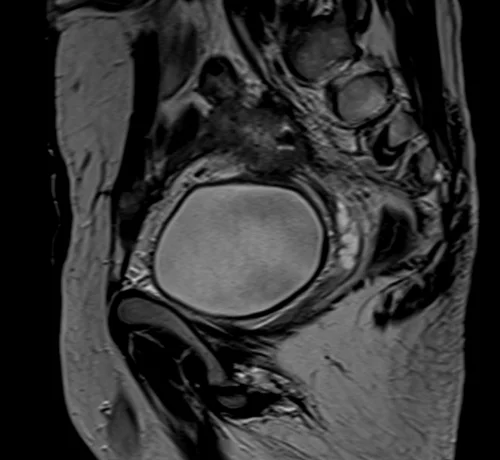

mri urinary bladder sagittal t2 image 3 - MRI